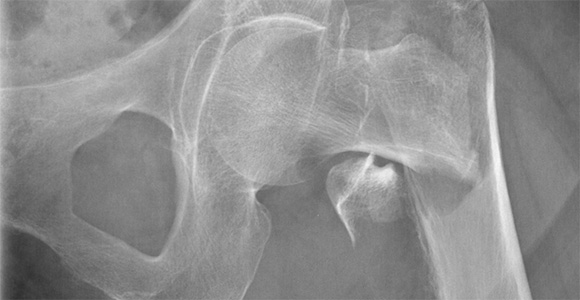

Ny undersøgelse: Fald i hoftebrud, flere hofteoperationer

Færre ældre får hoftebrud, men flere får nye hofter på grund af slidgigt.

En ny undersøgelse fra Syddansk Universitet og Københavns Universitetshospital Bispebjerg viser en faldende hyppighed af hoftebrud blandt ældre, men en stigning i hofteoperationer.

Forskerne har fundet en markant nedgang i hoftebrud blandt ældre. Denne positive udvikling skyldes formentlig bedre behandling af knogleskørhed, forebyggelse af fald, øget fysisk aktivitet og færre rygere.

Samtidig med faldet i antal hoftebrud er antallet af hofteoperationer steget, især blandt de ældste.

Nedgang i hoftebrud: - Blandt personer fra 80 til 104 år er hyppigheden af hoftebrud faldet med 35% til 40%.

Stigning i operationer relateret til hoftebrud: - Andelen af personer, der får ny hofte efter et brud, er steget med 50% til 70%. Stigningen er størst hos personer over 75 år.

Stigning i operationer relateret til slidgigt: - Hyppigheden af hofteoperationer udført for at behandle slidgigt hos personer i aldersgruppen 75 til 99 år er steget markant. Stigningen ligger på mellem 60% og 100%, hvilket indikerer næsten en fordobling af hyppigheden af sådanne operationer i denne aldersgruppe over den angivne periode.